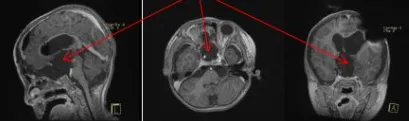

为保障患儿安全及提高切除率,巴教授与Concezio Di Rocco教授决定实施联合手术。通过额骨颅骨开颅术和大脑半球间穹窿入路切除肿瘤至Monro孔(室间孔),并沿脑室壁向中脑行进。右侧视神经被肿瘤浸润包裹,但左侧视神经被小心地从肿瘤肿块中剥离,垂体腺和垂体柄得到妥善保护,无术中并发症。第三脑室占位完全切除,鞍上占位基本全切,视神经及周围血管保持完整。

术后结果

拔管后患儿四肢活动正常。在密切监测血钠及液体平衡情况下,调整去氨加压素用药。返回普通病房后,巴教授与内分泌学家协作,使用去氨加压素治疗尿崩症并优化垂体激素替代方案。患儿顺利出院,临床症状较入院前明显改善。